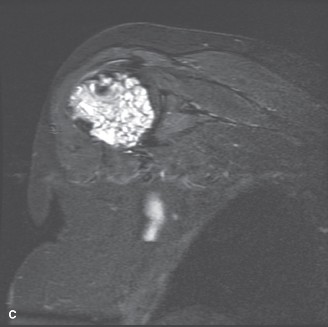

Figure 8–17 C

The correct answer is (A). Chondrosarcoma is a malignant cartilage-producing tumor. Three grades exist, in addition to a dedifferentiated form, and histopathologic examination of these lesions is not as reliable predictor of grade as in other lesions. For this reason, evaluation of the imaging is critical in determining the appropriate management. Location is important to the diagnosis of these lesions; for example, lesions in the hand are most commonly benign enchondromas, while those in the scapula are more commonly malignant. These tumors have little or no sensitivity to chemotherapy and radiation; therefore surgical resection is the primary treatment. For grade 1 lesions of the extremities, which are locally aggressive but have limited, if any, potential to metastasize, intralesional curettage and bone grafting is an accepted treatment with low recurrence rate. Pelvis lesions of any grade generally have a poorer prognosis, so wide resection is preferred in

the pelvis even for grade 1 chondrosarcoma. An open surgical biopsy is performed. Biopsy slide is shown inFigure 8–18A and B. Treatment for this patient should consist of: A. Preoperative radiation and wide resection with reconstruction